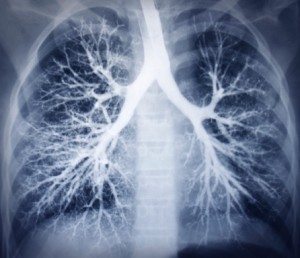

Lupus affects lungs, leads to pleuritis, pneumonitis and pulmonary hypertension

Lupus is an autoimmune disease that often impacts the lungs, and research shows pulmonary complications with this disease can lead to pleuritis, pneumonitis and pulmonary hypertension.

When a person has a lung infection it usually affects their airway and lung tissue, but with lupus it seems that it can impact all compartments of the lungs and include pleuritis, which is inflammation of the linings around the lung, as well as pulmonary hypertension (high blood pressure that occurs in the arteries in the lungs). Those with lupus and lung problems can also get pneumonitis, inflammation of the walls of the alveoli in the lungs, normally caused by a virus.

Lupus and lung involvement are not automatic. In other words, just because you have lupus does not mean that you will have lung problems. Studies suggest that about 50 percent of those with lupus with eventually suffer from some sort of lung disease. Medical researchers think it is important that patients fully understand the complications that could arise so they can be addressed at the first signs – before symptoms get too out of control. Continue reading…